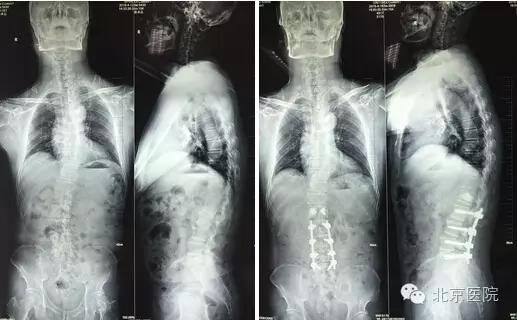

近日,北京医院骨科成功治疗一名合并小儿麻痹症的脊柱侧弯患者。患者陈某某,男,62岁。年幼时因小儿麻痹症导致左下肢无力,主要靠右下肢行走。随着年纪增大,出现脊柱侧弯、腰疼,近年来腰疼逐渐加重伴右下肢放射痛,间歇性跛行小于100米,右下肢无法完成既往行走功能。到当地医院就诊,经针灸、理疗、药物等多种方法对症治疗无法缓解,后到北京医院骨科就诊。

患者由张啟维副主任医师接诊。他根据病情及临床资料诊断考虑患者属于小儿麻痹症后遗症导致的脊柱侧弯,随着年龄增大,脊柱侧弯发生退变并加重,导致椎管狭窄。椎管狭窄压迫神经导致患者出现腰疼及右下肢神经肌肉功能障碍。而患者由于小儿麻痹导致左下肢长期无力,如果其右下肢再出现神经肌肉功能障碍,今后将面临双下肢瘫痪,永远不能行走、坐轮椅的风险,手术治疗很必要。但患者合并糖尿病、高血压等内科疾病。既往有骨质疏松症导致的股骨颈骨折病史,病情比较复杂,客观上讲,麻醉及手术的风险较大。如手术过程出现意外,患者极有可能面临瘫痪的危险。因此,此手术极具挑战。

入院后,骨科闵楠医生带领住院医师团队积极完善各项检查,对患者进行术前安全评估及准备。张啟维副主任医师对患者进行了认真而仔细的查体,并结合病人症状及影像学资料为患者制定了一套安全有效的治疗方案。在方案制定过程中,张啟维副主任医师既考虑到充分减压以解除患者术前神经压迫症状,又考虑到对患者侧弯进行有效矫形以恢复脊柱力线平衡。同时,还要结合患者合并多种内科疾病、身体条件较差的实际情况,尽量在保证效果的前提下将手术小型化、微创化,以降低手术及麻醉给患者带来的创伤,进而降低手术麻醉风险。张啟维副主任医师结合自己出国学习所获得的先进技术,根据实际病情为患者制定了最适合的微创切开手术方案:即后柱截骨(PCO Posteiror Column Osteotomy)矫形联合腰椎4-5椎间融合加后路固定融合术。PCO后柱截骨术手术保留了椎板、棘突,既减少了手术神经、硬膜的损伤及出血,又为后柱植骨融合准备了良好的植骨床,也减少了临近节段退变几率,成为治疗侧弯畸形切开手术微创化的重要术式。是目前国际脊柱畸形手术微创化发展的重要成就之一。

经过完备的术前检查及手术方案,骨科医生在麻醉科黄兵副主任医师及手术室的密切配合下,张啟维副主任医师亲自主刀,在徐宏兵主任医师的帮助下,为患者成功施行脊柱侧弯矫形手术。手术历经3个多小时。术后第1天患者的下肢神经症状就得到缓解,术后第3天患者即可下地行走,术后第6天即出院。